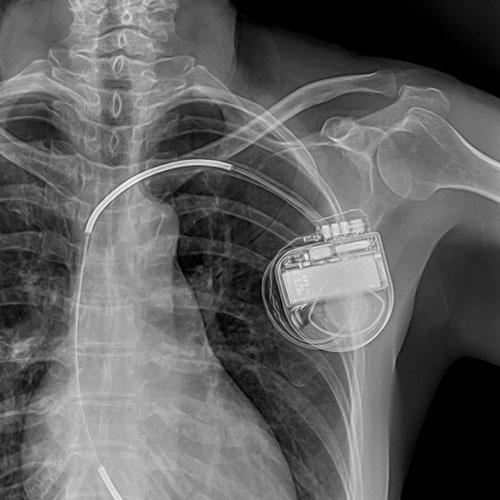

Аперацыя праводзіцца пад мясцовай анестэзіяй. Праз скурны разрэз (даўжынёй не больш за 5 см) пад рэнтген-кантролем да сэрца заводзяцца і фіксуюцца электроды. Затым усталёўваецца кардыявертэр-дэфібрылятар (ІКД).